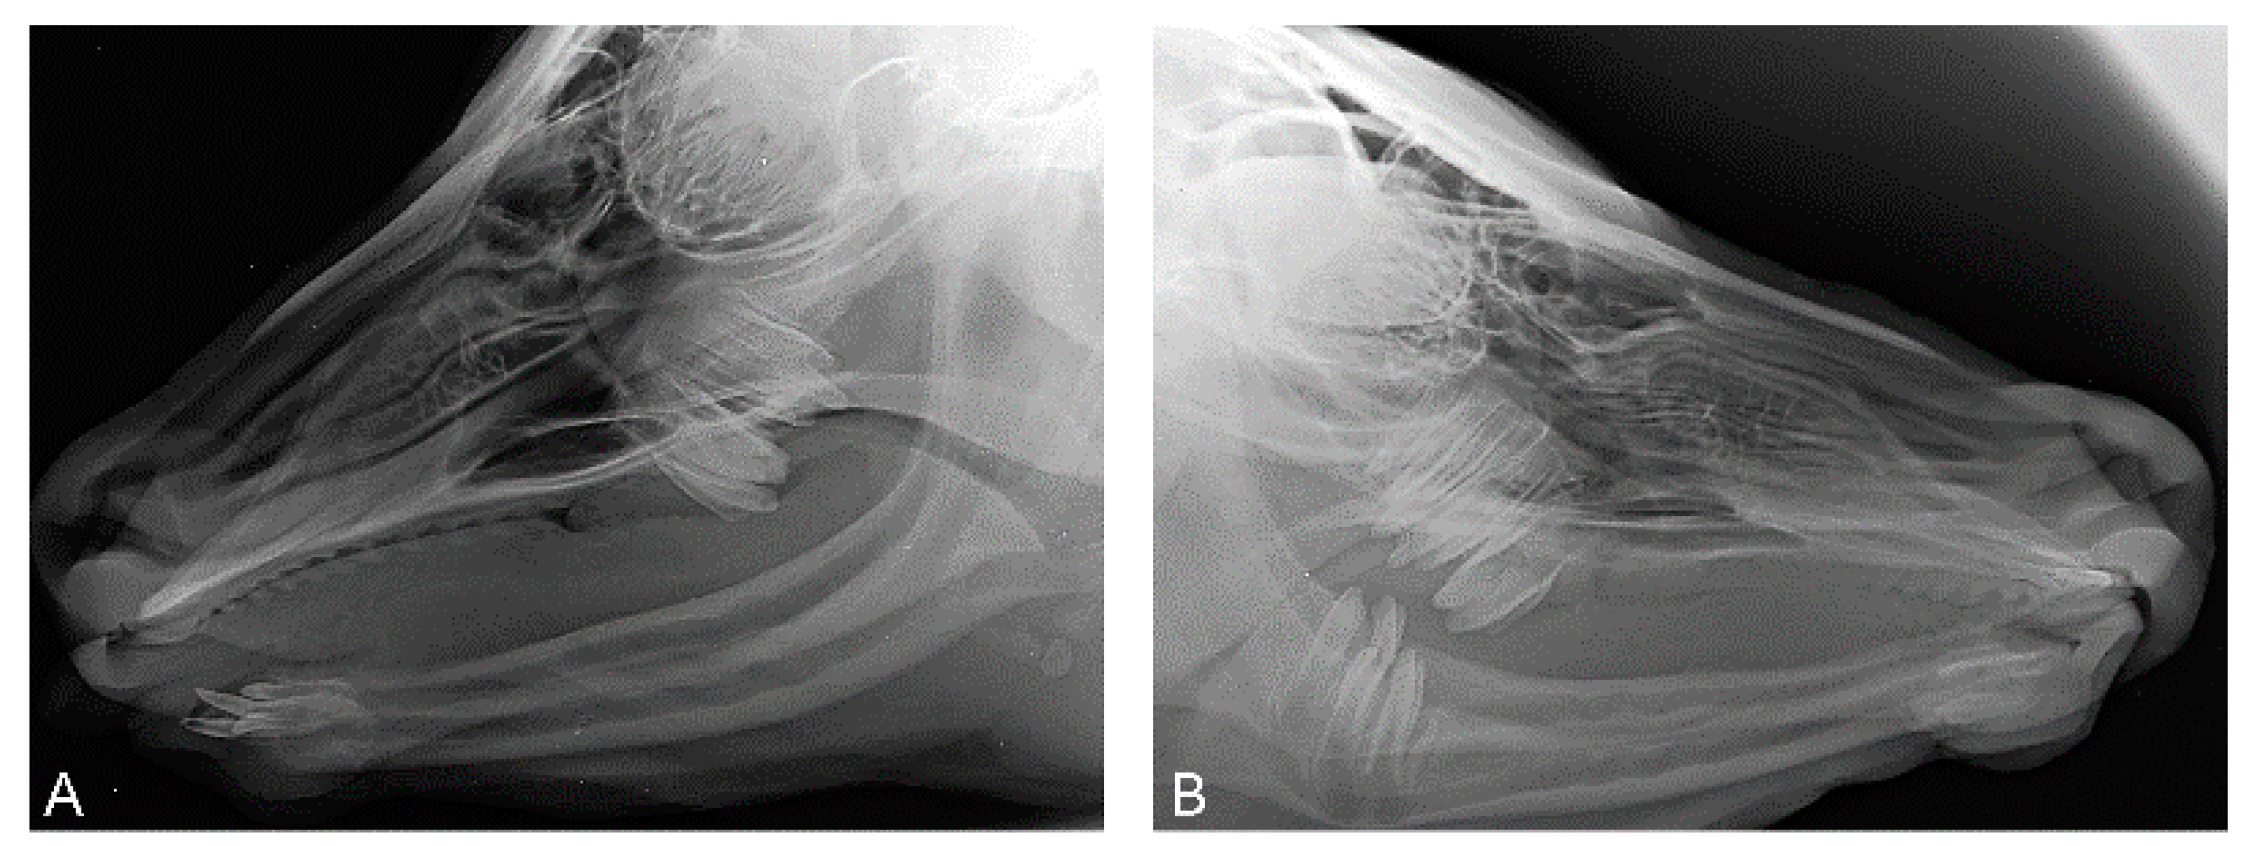

At the age of 7 weeks, case 1 had developed one lateral incisor (I3) on each side (Figure 3).

Radiographs of the head of case 1 at the age of seven weeks (A) and of the head of case 2 at the age of four months (B). (A) Latero-lateral view. Four maxillary molars, two on each side, were visible. Apart from the two erupted incisors, two shorter, not erupted, also pointed canines were seen. A total of eight teeth were present. (B) Latero-lateral view. Six molars, three on each side on both sides, were visible. Incisors and canines were absent.

These incisors (case 1) were visible as rice grain-like structures at the mandible. By the tenth week, conic and up to 1.3 cm long teeth had grown. At the age of 7 months, the canine on the left side broke through the gums and the canine on the right was covered by a gum cap (Figure 4). In case 2, neither incisors nor canines developed up to the age of 11.5 months. In case 3, at the age of ten weeks, a spiky incisor had broken through the gum on the left side.

At the age of 7 weeks, the presence of each two molars on each side were seen on the X-rays of case 1, but mandibular premolars were absent. Case 2 did not show incisors or canines at clinical examination or on the X-rays at the age of 4 months. Using X-rays, two maxillary molars on each side and the mandibular molars on both sides of case 2 were observed. In case 3, a spiky incisor (I3) broke through the gums on the left side at the age of ten weeks. At the age of four months of case 3, computed tomography of the head demonstrated the presence of canines on both sides of the mandible, two molars on each side of the maxilla and one molar on both sides of the mandible. At the age of 7 months, the canines broke through the gums on both sides. The right-sided canine stayed short. The development stages of the canines resembled those of case 1. No further development of teeth was observed throughout the rest of the lives of all three cases.